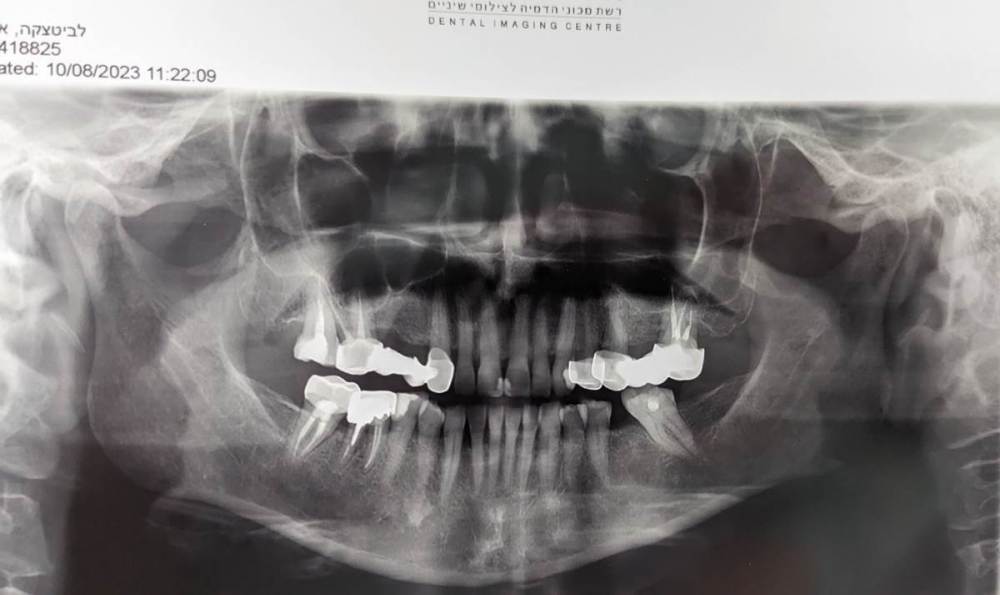

после сильного стресса нарушился прикус. на верхней челюсти боковые зубы сдвинулись вовнутрь, а передние ушли немного вперёд.

в детстве были полностью вырваны 4 и 5 зубы справа, и 6 слева. на боковых зубах справа и слева стоят рандолевые мосты - по четыре жевательных зуба (справа 3, 4, 5, 6 зубы. слева - 4 это отдельная коронка, а 5, 6, 7 - мост). хочу поменять эти мосты на металлокерамические. и есть желание выровнять кривой зуб (2 справа).

врач, который ставит коронки, говорит что новые мосты полностью исправят прикус, но есть сомнения, ведь передние зубы мосты не затронут.

вопрос - можно ли будет исправить прикус после замены старых железных мостов на металлокерамические ?